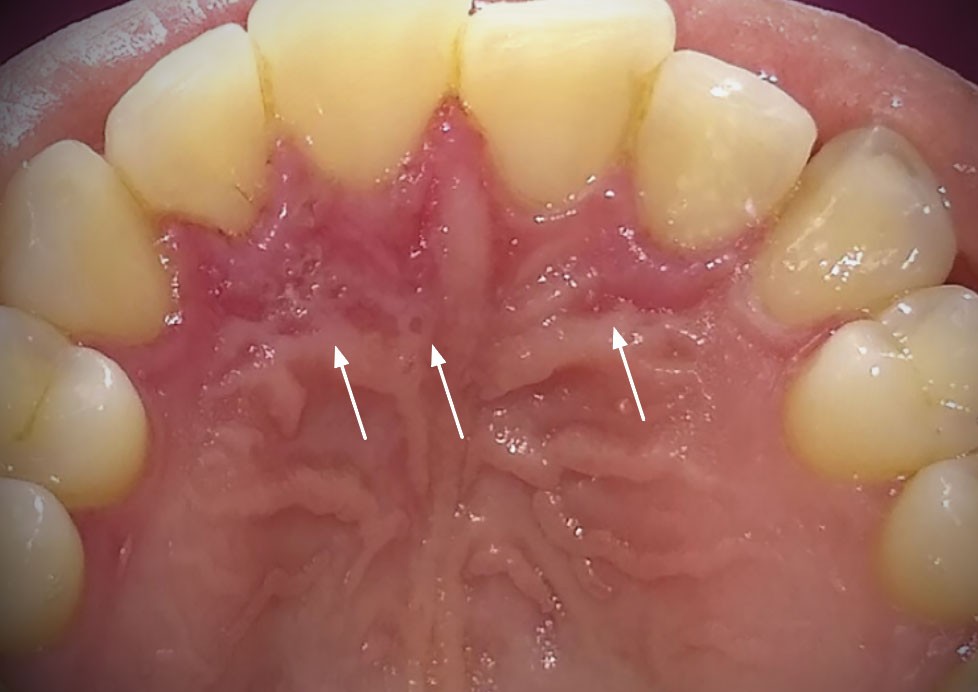

Présence de zones d’érosions post-vésiculeuses regroupées en « bouquet » en palatin des 12, 11 et 22 (fig. 1a) et au niveau de la gencive marginale de la 23 (fig. 1b). Les muqueuses affectées étaient enflammées et sensibles au toucher. Pas d’adénopathie cervico-faciale palpable et pas d’atteinte extra-orale.